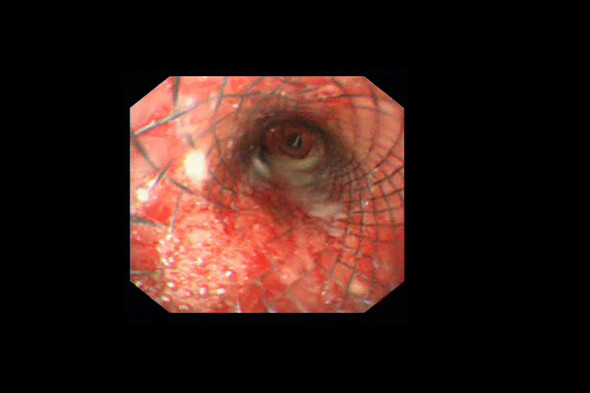

24小时后复查气管镜及CT提示:食管气管相通的瘘口完全封堵。患者进食恢复,未再呛咳,发热、咯痰也明显减轻。气管覆膜支架植入封堵瘘口术,改善了气管食管瘘病人的生存质量,延长了病人生存时间,得到患者及家属的一致好评。

支架后